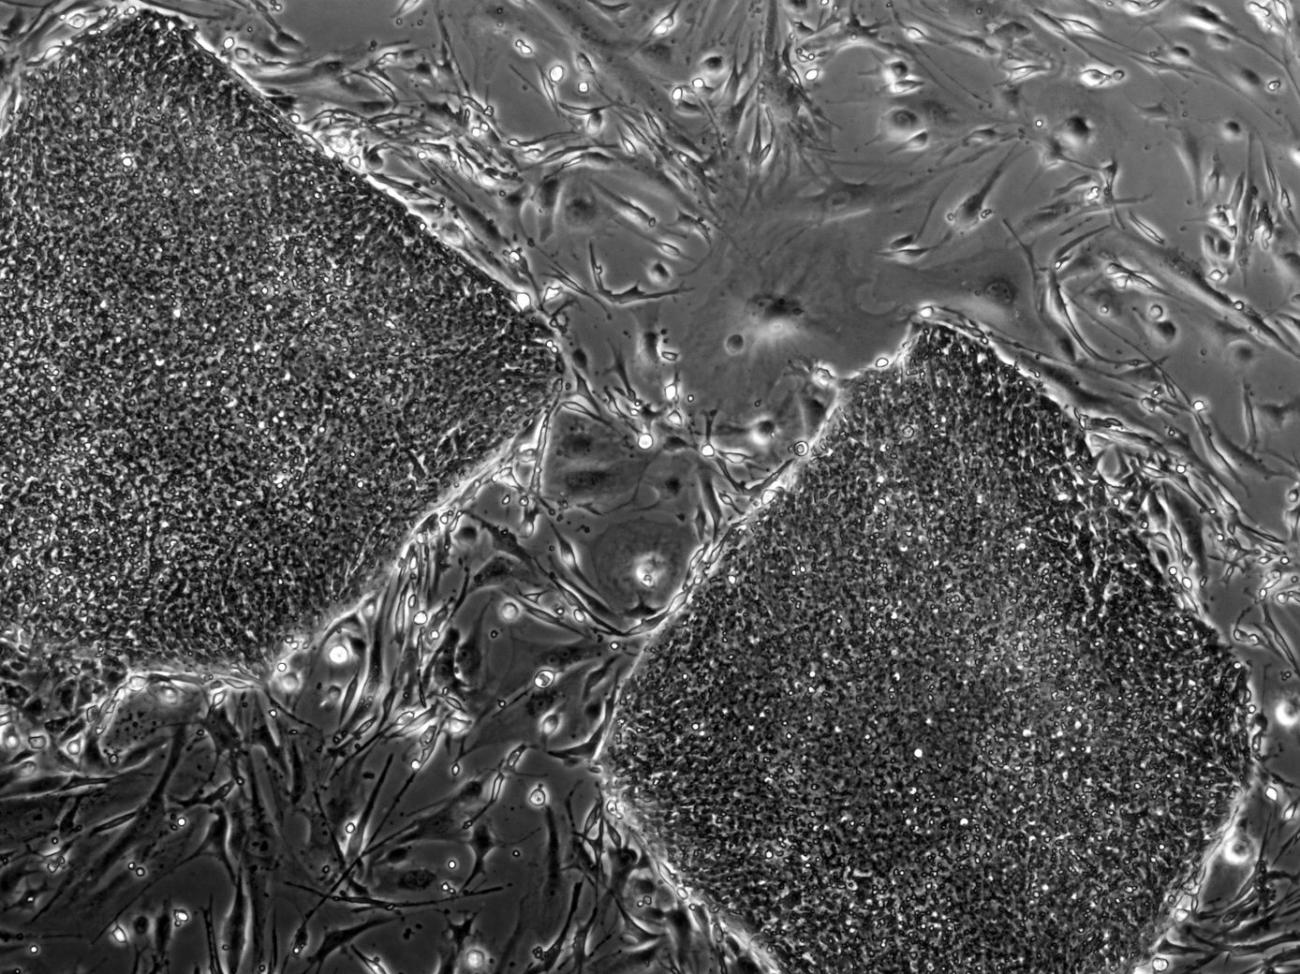

In 1998, scientists succeeded in isolating human embryonic stem cells, or hESCs, for the first time. Since then, the more versatile and flexible regenerative potential of hESCs has proved vital to scientific research, enabling scientists to learn about human developmental processes that would otherwise be inaccessible. Unlike tissue-specific stem cells, hESCs have two distinct capabilities: They can replicate indefinitely, and they’re pluripotent, meaning they can produce the more than 200 cell types found in the human body through a process called differentiation The process by which stem cells transform into specific, specialized cell types with distinct functions and features. differentiation The process by which stem cells transform into specific, specialized cell types with distinct functions and features..

iPSCs originate from cells — such as skin or blood — that are removed from a person and reprogrammed back to a pluripotent state. Like hESCs, these reprogrammed cells can replicate indefinitely as well as differentiate into any cell type in the human body. Since iPSCs are made from a patient’s own cells, therapies created from these cells could potentially be perfectly matched to the patient.

All of the human embryonic stem cells currently used in research come from cell lines that have been approved for research and registered with the National Institutes of Health. The original hESCs used to establish these lines come from embryos that are donated from consenting individuals or couples who have unused embryos after in vitro A process, procedure or study performed in a test tube or lab dish rather than in a living organism. in vitro A process, procedure or study performed in a test tube or lab dish rather than in a living organism. fertilization, or IVF, procedures. The embryonic stem cells are isolated from the inner cell mass of the blastocyst An embryo in its very early stage, usually 5 to 6 days old, that has not implanted or attached to a uterus. It is made up of a small group of inner cells, which will develop into the embryo, and an outer layer of cells, which will develop into the placenta and amniotic membranes. blastocyst An embryo in its very early stage, usually 5 to 6 days old, that has not implanted or attached to a uterus. It is made up of a small group of inner cells, which will develop into the embryo, and an outer layer of cells, which will develop into the placenta and amniotic membranes., a stage in early human embryonic development that occurs within the first four to six days after fertilization. Once hESCs are isolated, the cells may be kept alive and multiplied under specific laboratory conditions. Visit the California Institute for Regenerative Medicine's page on stem cell research to learn more about this process.